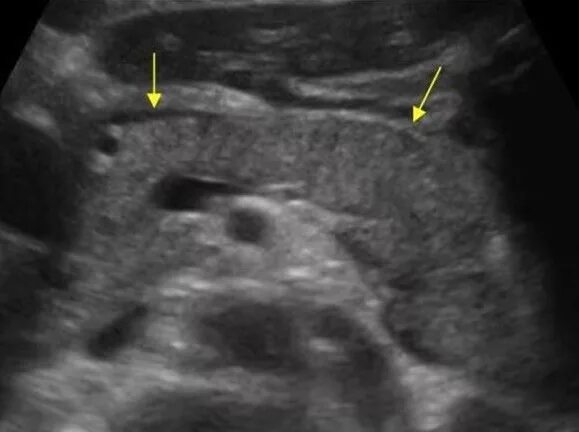

Узи шип